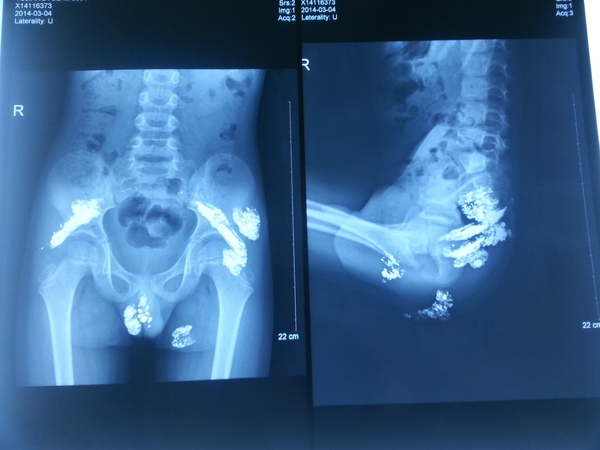

307医院儿科主任何玉玺介绍,奇奇入院时是由家属抱着来的,身体虚弱,体重仅30斤左右。经过查体,在其臀部、阴囊、双侧髂骨下等全身多处发现大量软组织包裹液态汞,术前监测数据显示,其体内血液中的汞含量超过正常值141倍、尿汞含量超过正常值1500倍。

“人体汞中毒本身就是非常特殊的病例,而如此大的剂量、如此小的年龄,在世界医学史上更是极其罕见。这一病例在世界范围内首次出现。”307医院院长刘素刚说,专家会诊后判断,这些汞在患儿体内至少已经存留5个月以上,因为大面积存在,对患儿心、肝、肾等重要脏器造成严重的损害,导致臀部皮肤出现破溃、引起高烧等诸多并发症,严重危及孩子生命。

“这么大剂量,通过药物驱汞清理不掉,只能靠手术。”307医院普外科专家尉承泽介绍,为避免大出血、汞包块破裂等意外情况出现,医院在手术前进行两个疗程的内科驱汞,待患儿生理指标稳定后进行了两次外科手术,共取出了6个含汞包块。第一次手术风险最大,难度最高,前后历经5个多小时,取出4个包块,3个部位在表皮组织,汞呈炮弹形状,1个部位在肌肉组织层面,汞呈现散落的菜花状,对手术剥离造成非常大的困难。幸运的是,两次手术都圆满成功。